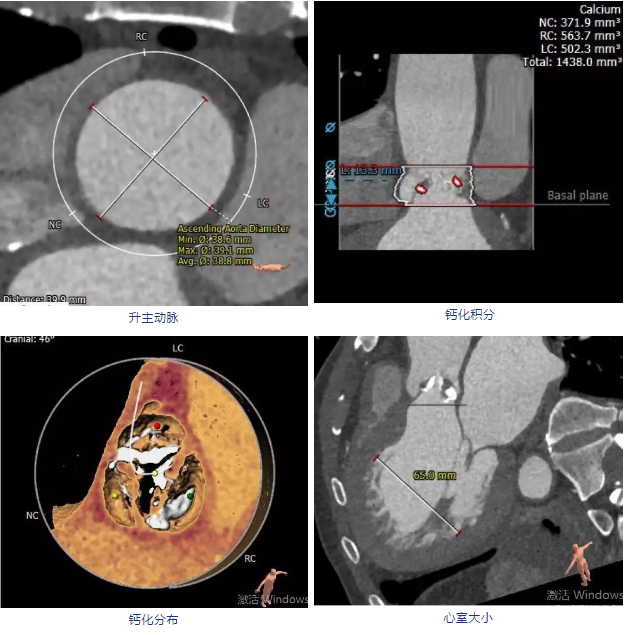

全主动脉CTA评估:

符合瓣膜性心脏病(主动脉瓣病变),升主动脉扩张;冠脉散在钙化并管腔狭窄,双侧胸腔积液。

CT分析:

建议术中球囊扩张确认冠脉风险,瓣膜型号推荐VenusA-Valve29号瓣膜,备选VenusA-Valve26号瓣膜。

三叶瓣,极重度钙化,瓣叶增厚,左无钙化粘连,瓣叶冗长,冠脉开口处瓣叶均有明细钙化,且对侧钙化团块存在,冠脉风险高,术中植入瓣膜前进行冠脉保护,颈动脉入路。